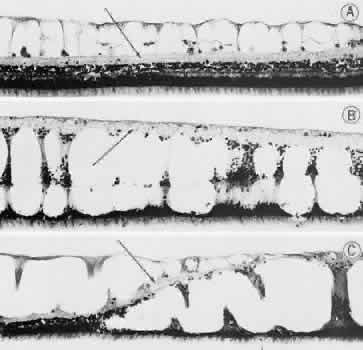

equator (Fig. 16).  Fig. 15. Typical and retinal cystoid degenerations. A. Degeneration of nerve fiber layer with persistence of delicate vertical

columns of Müller's cells. Superficial capillary plexus courses

through the cystoid cavities, and surviving ganglion cells are subtended

on the inner aspect of the inner plexiform layer (arrow). Outer retinal layers are well preserved. B. Extensive degeneration of middle retinal layers with broad cellular columns (between

cystoid cavities) composed of Müller's cells

and remnants of outer plexiform layer and inner nuclear layer (vertically

stretched). Outer nuclear layer also shows degeneration. Inner plexiform

layer (arrow) is intact. C. Overlapping reticular (on the left) and typical (on the right) cystoid

degeneration. Note combined degenerative effect on the inner plexiform

layer (arrow) of both types of cystoid degeneration. Superficial small arteriole retards

progression of reticular cystoid degeneration. (Hematoxylin-eosin, × 250.) (Foos RY: Senile retinoschisis: Relationship to cystoid degeneration. Trans

Am Acad Ophthalmol Otolaryngol 1970;74:33.) Fig. 15. Typical and retinal cystoid degenerations. A. Degeneration of nerve fiber layer with persistence of delicate vertical

columns of Müller's cells. Superficial capillary plexus courses

through the cystoid cavities, and surviving ganglion cells are subtended

on the inner aspect of the inner plexiform layer (arrow). Outer retinal layers are well preserved. B. Extensive degeneration of middle retinal layers with broad cellular columns (between

cystoid cavities) composed of Müller's cells

and remnants of outer plexiform layer and inner nuclear layer (vertically

stretched). Outer nuclear layer also shows degeneration. Inner plexiform

layer (arrow) is intact. C. Overlapping reticular (on the left) and typical (on the right) cystoid

degeneration. Note combined degenerative effect on the inner plexiform

layer (arrow) of both types of cystoid degeneration. Superficial small arteriole retards

progression of reticular cystoid degeneration. (Hematoxylin-eosin, × 250.) (Foos RY: Senile retinoschisis: Relationship to cystoid degeneration. Trans

Am Acad Ophthalmol Otolaryngol 1970;74:33.)